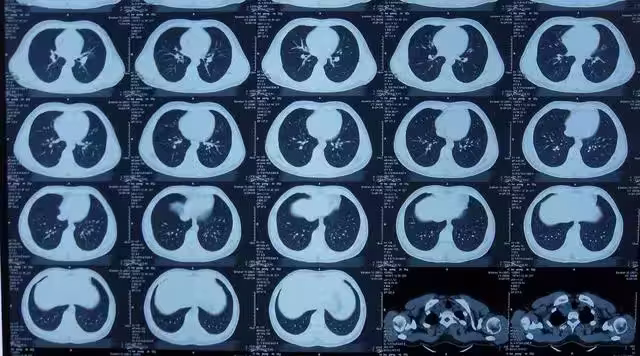

那多大劑量會誘發癌症呢?

由於CT檢查的輻射劑量在安全範圍內,許多人可能會認為CT檢查是相對安全的,可以放心進行,然而,這並不意味著CT檢查沒有任何風險。

事實上,CT檢查仍然存在患癌症的風險,根據相關研究,一次效劑量為10mSv的成人腹部CT檢查將使癌症風險增加1/2000。

此外,國際輻射防護委員會(I-CRP)的研究數據表明,CT全身掃描體檢將使受檢者的輻射致癌風險增加約8%。

這意味著,如果一個人經常接受CT檢查,他們患癌症和遺傳病的風險會隨著接觸次數的增加而增大。